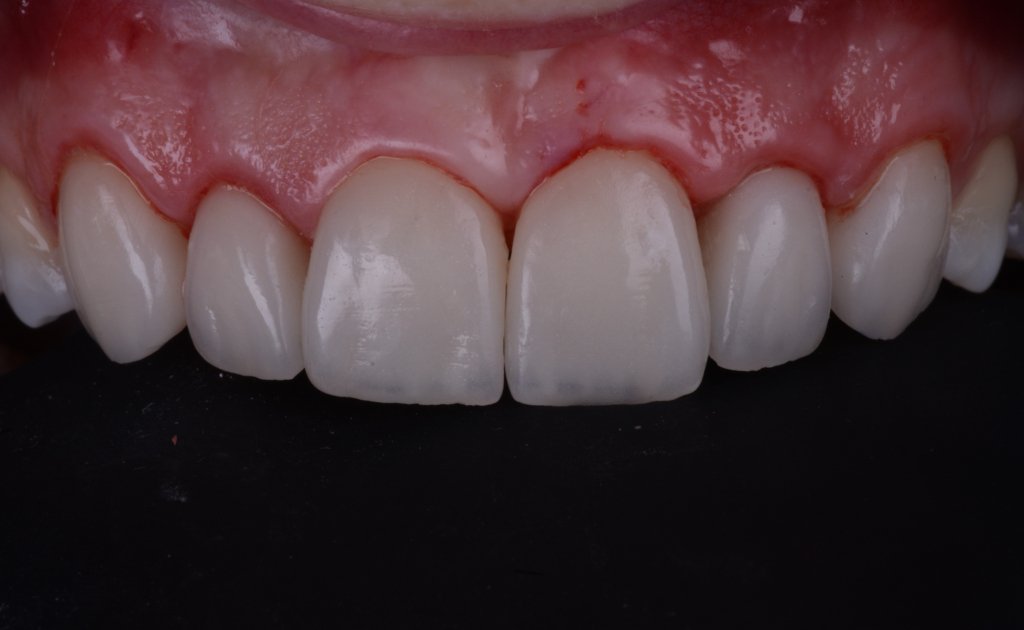

El momento más «bonito» para ti, para la paciente, para la auxiliar (Karla), y para Nacho…a ver si no rompemos sus MARAVILLAS (pero la culpa es siempre mía, que tallo cada vez menos)

Keep calm trás la retirada del Dique, esta encía volverá a su sitio (si habéis hecho bien la cirugía por supuesto).

No me asusta esta ligera inflamación, al revés se que están pasando cosas buenas, la encía se esta estabilizando y engordando según los principios de la técnica BOPT. Así que tengo tiempo para disfrutar simplemente del trabajazo de Nacho.